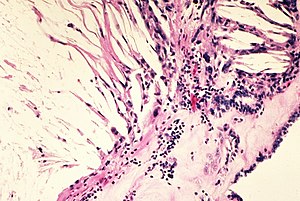

Ключевую роль в понимании патологического значения холестерина сыграл российский патолог Николай Николаевич Аничков, впервые продемонстрировавший роль холестерина в развитии экспериментального атеросклероза в начале XX века. Современное понимание молекулярных механизмов холестеринового метаболизма было заложено работами Конрада Блоха и Феодора Лайнена, удостоенных Нобелевской премии в 1964 году за расшифровку путей биосинтеза холестерина и жирных кислот.